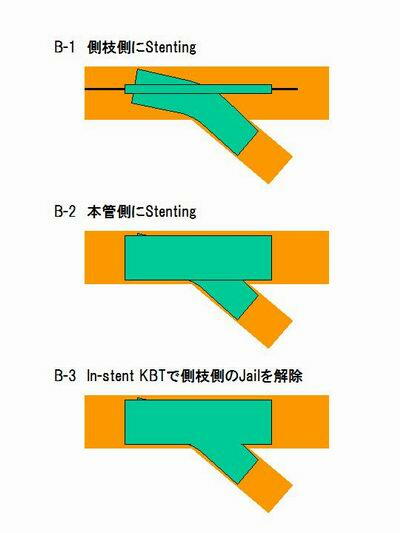

先日、CypherのベースになっているVelocityを使ってYステントの

実験をしてみました。ガイダント社で作成されたポリビニールアル

コール(PVA)製の冠動脈模型の中で4mmと3mmのVelocityを使

ってYステントを施行しました。deployはどちらも16atmで、最終の

In stent-KBTは8atmで行っています。Yステント施行後に熱湯の

中でPVAを溶解し、ステントのみを写真撮影しています。結果は

添付の写真に示すとおりで、従来より指摘されていたとおりに、

本管にくびれができています。closed cell typeのステントの問題

点が明瞭に示されている結果でした。本管側が3mmを超えるよう

な状況下でのCypher-Y stentingにはやはり問題がありそうです。

Crush や Reverse Crush の問題点は、(1) Strut free の部分が

分岐部に形成され、側枝側の再狭窄率を上げると予想されること、

(2) 血管壁に全く密着していないステント部分が大量に残り、慢性期

の stent thrombosis の原因になる可能性があること、の2点です。

添付した図に示しましたが、Crush を行うと、模式図Aで示される様な

配置には決してならず、必ず模式図Bのようになります。側枝側に入れ

る Cypherはその硬さゆえに本管をまたいで分岐とは反対側に近位部

が来る形で展開されます。その結果、本管側の Cypher で Crushす

る際には、分岐方向とは 90度ずれた状態(模式図Bでは図の向こう

側)に Crushされます。結果として、分岐部の2本のステントの位置関

係は3次元的にねじれた複雑な状態になっています。Crush 後の In-

stent KBT を行う際に、Wireを近位側より通すことでstrutのかたより

を防げると言われていますが、実際には上記のような空間配置となって

いるために、wireがどこを通っても Crushされたステントの180度反対

方向に Strut free space(strutが血管壁から浮いた部分も含めて

ですが) がかなりできてしまうことがわかりました。

|

実験では、stent strut と血管壁の密着度を判定できる「ある工夫」

をしています。その結果、血管内に浮いた状態で存在する金属量は

Revres Crush > Crush >>> Y-stenting の関係にあることが示されて

います。